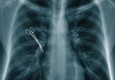

Kirurzi zaboravili lopaticu u tijelu pacijentice nakon operacije

Češki kirurzi iz bolnice u gradu Ivancice suspendirani su nakon što je otkriveno da su u tijelu pacijentice nakon operacije zaboravili 30 centimetara dugačku lopaticu. Kirurški instrument pronađen je tek pet mjeseci nakon što se nevjerojatna pogreška dogodila, a…